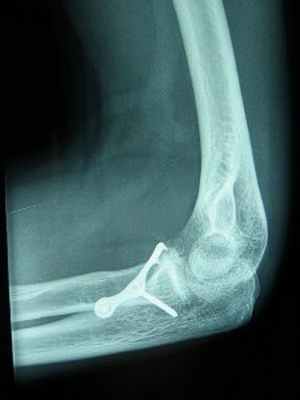

Перелом локтевого отростка • Причины: прямая травма, резкое сокращение трёхглавой мышцы плеча • Клиническая картина: припухлость локтевого сустава, рука выпрямлена, свисает; пассивные движения причиняют боль, активное разгибание при переломе со смещением невозможно, треугольник Хютера деформирован, вершина локтевого отростка находится выше линии, соединяющей надмыщелки плеча • Лечение •• Переломы без смещения: гипсовая повязка на 3–4 нед в положении сгибания предплечья в локтевом суставе на 90–110°, в среднем положении между пронацией и супинацией •• Перелом со смещением более 5 мм — остеосинтез •• ЛФК.

При переломе локтевого и венечного отростка без смещения накладывают гипсовую повязку сроком на 3-4 недели. При смещении фрагментов больше чем на 5мм при переломе локтевого отростка проводят оперативное вмешательство методом остеосинтеза (соединение костных отломков при помощи фиксирующих конструкций, которые обеспечивают неподвижность костных фрагментов). При вклинивании осколка в локтевой сустав при переломе венечного отростка оперативно удаляют этот фрагмент.